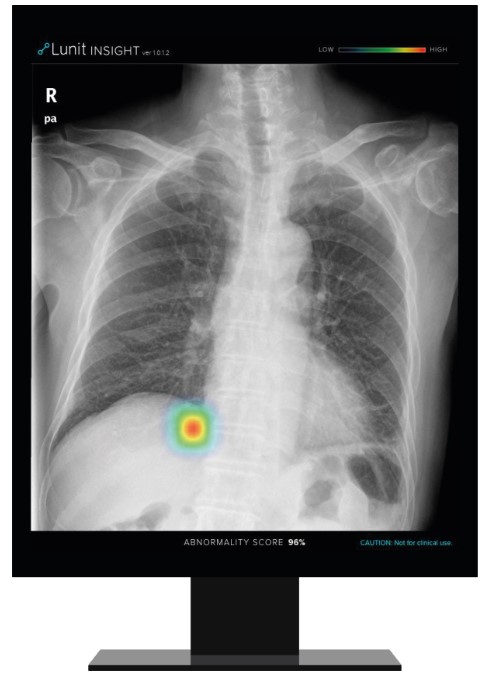

루닛은 최근 필립스(Philips) 본사와 파트너십을 체결했다. 이번 파트너십으로 루닛의 폐질환 진단 보조 소프트웨어 '루닛 인사이트 CXR'은 필립스의 흉부 엑스레이 진단 플랫폼에 탑재돼 전 세계 의료 현장에 공급된다. 필립스는 GE 헬스케어, 지멘스와 함께 세계 3대 의료기기 기업으로 꼽힌다. 업계에 따르면 필립스의 글로벌 흉부 엑스레이 시장 점유율은 20% 가량에 달한다. 다안 반 마넨(Daan Van Manen) 필립스 진단용 엑스레이 부문 총괄 매니저는 루닛의 기술력에 대해 "루닛 AI 알고리즘의 판독 정확도와 효율성은 이미 국제 학술지 등을 통해 입증됐다"고 평가했다.

앞서 루닛은 GE 헬스케어와 일본 최대 의료영상장비 업체인 후지필름과도 파트너십을 체결했다. 두 회사에 이어 필립스와의 파트너십으로 글로벌 엑스레이 시장의 약 50% 정도 수준에 이르는 판로를 확보했다는 게 루닛 측의 설명이다.